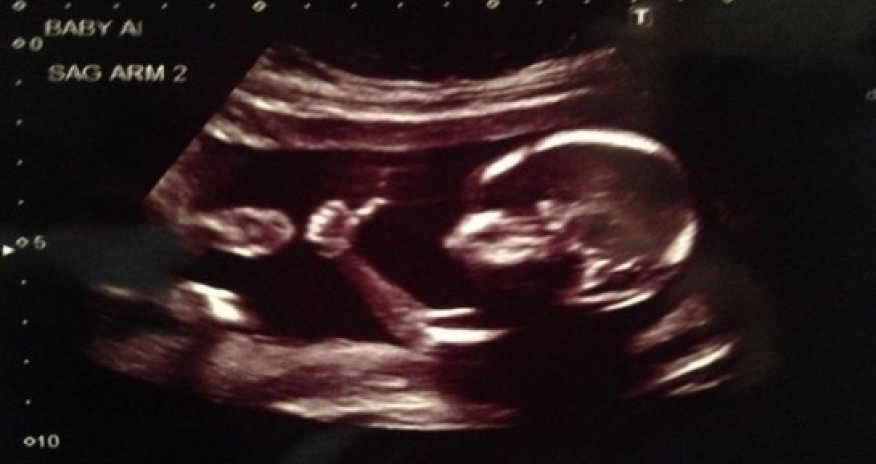

Baby gives thumbs-up in ultrasound photo

A baby is already a viral sensation and hasn't even born yet. And It's all because of a gesture in an ultrasound photo.

The fetus was captured flashing what looks like the thumbs-up sign in an ultrasound picture taken last week.

The ultrasound image on Reddit was posted on August 28 under the username meancloth, saying "ultrasound result looks good."

Some have nicknamed the baby the "Fonzie fetus," after the iconic cool guy character in the classic television series Happy Days, according to AOL.com.

The father, Brandon Hopkins, told HLN-TV that his wife is expecting twins and the babies are due to arrive in January. The couple will find out the sex of the babies soon. Hopkins said his brother called and told him, 'Your babies are famous'!